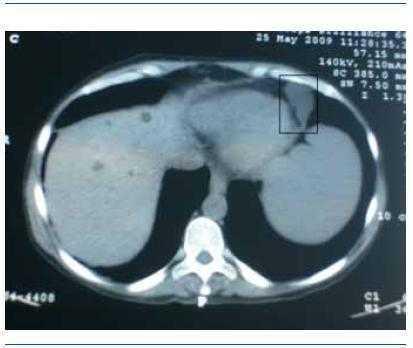

Mujer de 46 años, con antecedentes familiares de enfermedad poliquística del adulto, que ingresó por insuficiencia renal avanzada, con creatinina sérica de 8 mg/dl y clínica urémica. En la exploración abdominal se palpaban dos masas gigantes polilobuladas en ambos flancos. La ecografía abdominal mostró riñones poliquísticos y múltiples quistes hepáticos de diferentes tamaños. Durante el ingreso presentó un cuadro febril con dolor abdominal en fosa ilíaca derecha, por lo que, ante la sospecha de quiste renal complicado, se solicitó un TAC tóraco-abdominal, que mostró la existencia de una imagen ovoidea de 8,4 x 2,1 cm, hipodensa, adyacente al lado izquierdo del pericardio, compatible con quiste pericárdico. Un ecocardiograma demostró la presencia de un derrame pericárdico leve asociado. Ante la presencia de un cultivo de orina positivo para Escherichia coli, se inició tratamiento antibiótico y remitieron la fiebre y el dolor. Actualmente la paciente está en programa de hemodiálisis periódica.

Figura 1. Imagen de quiste adyacente al lado izquierdo del pericardio